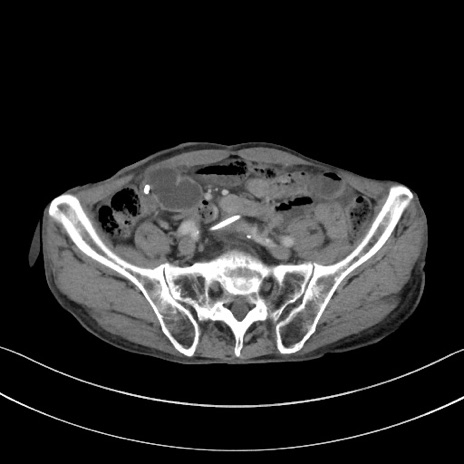

症例3(横断像)

【症例】 70歳代男性

【主訴】右鼠径部腫瘤、疼痛

【現病歴】本日朝より上記主訴あり、受診。

【既往歴】膀胱癌にて膀胱全摘、両側尿管皮膚瘻